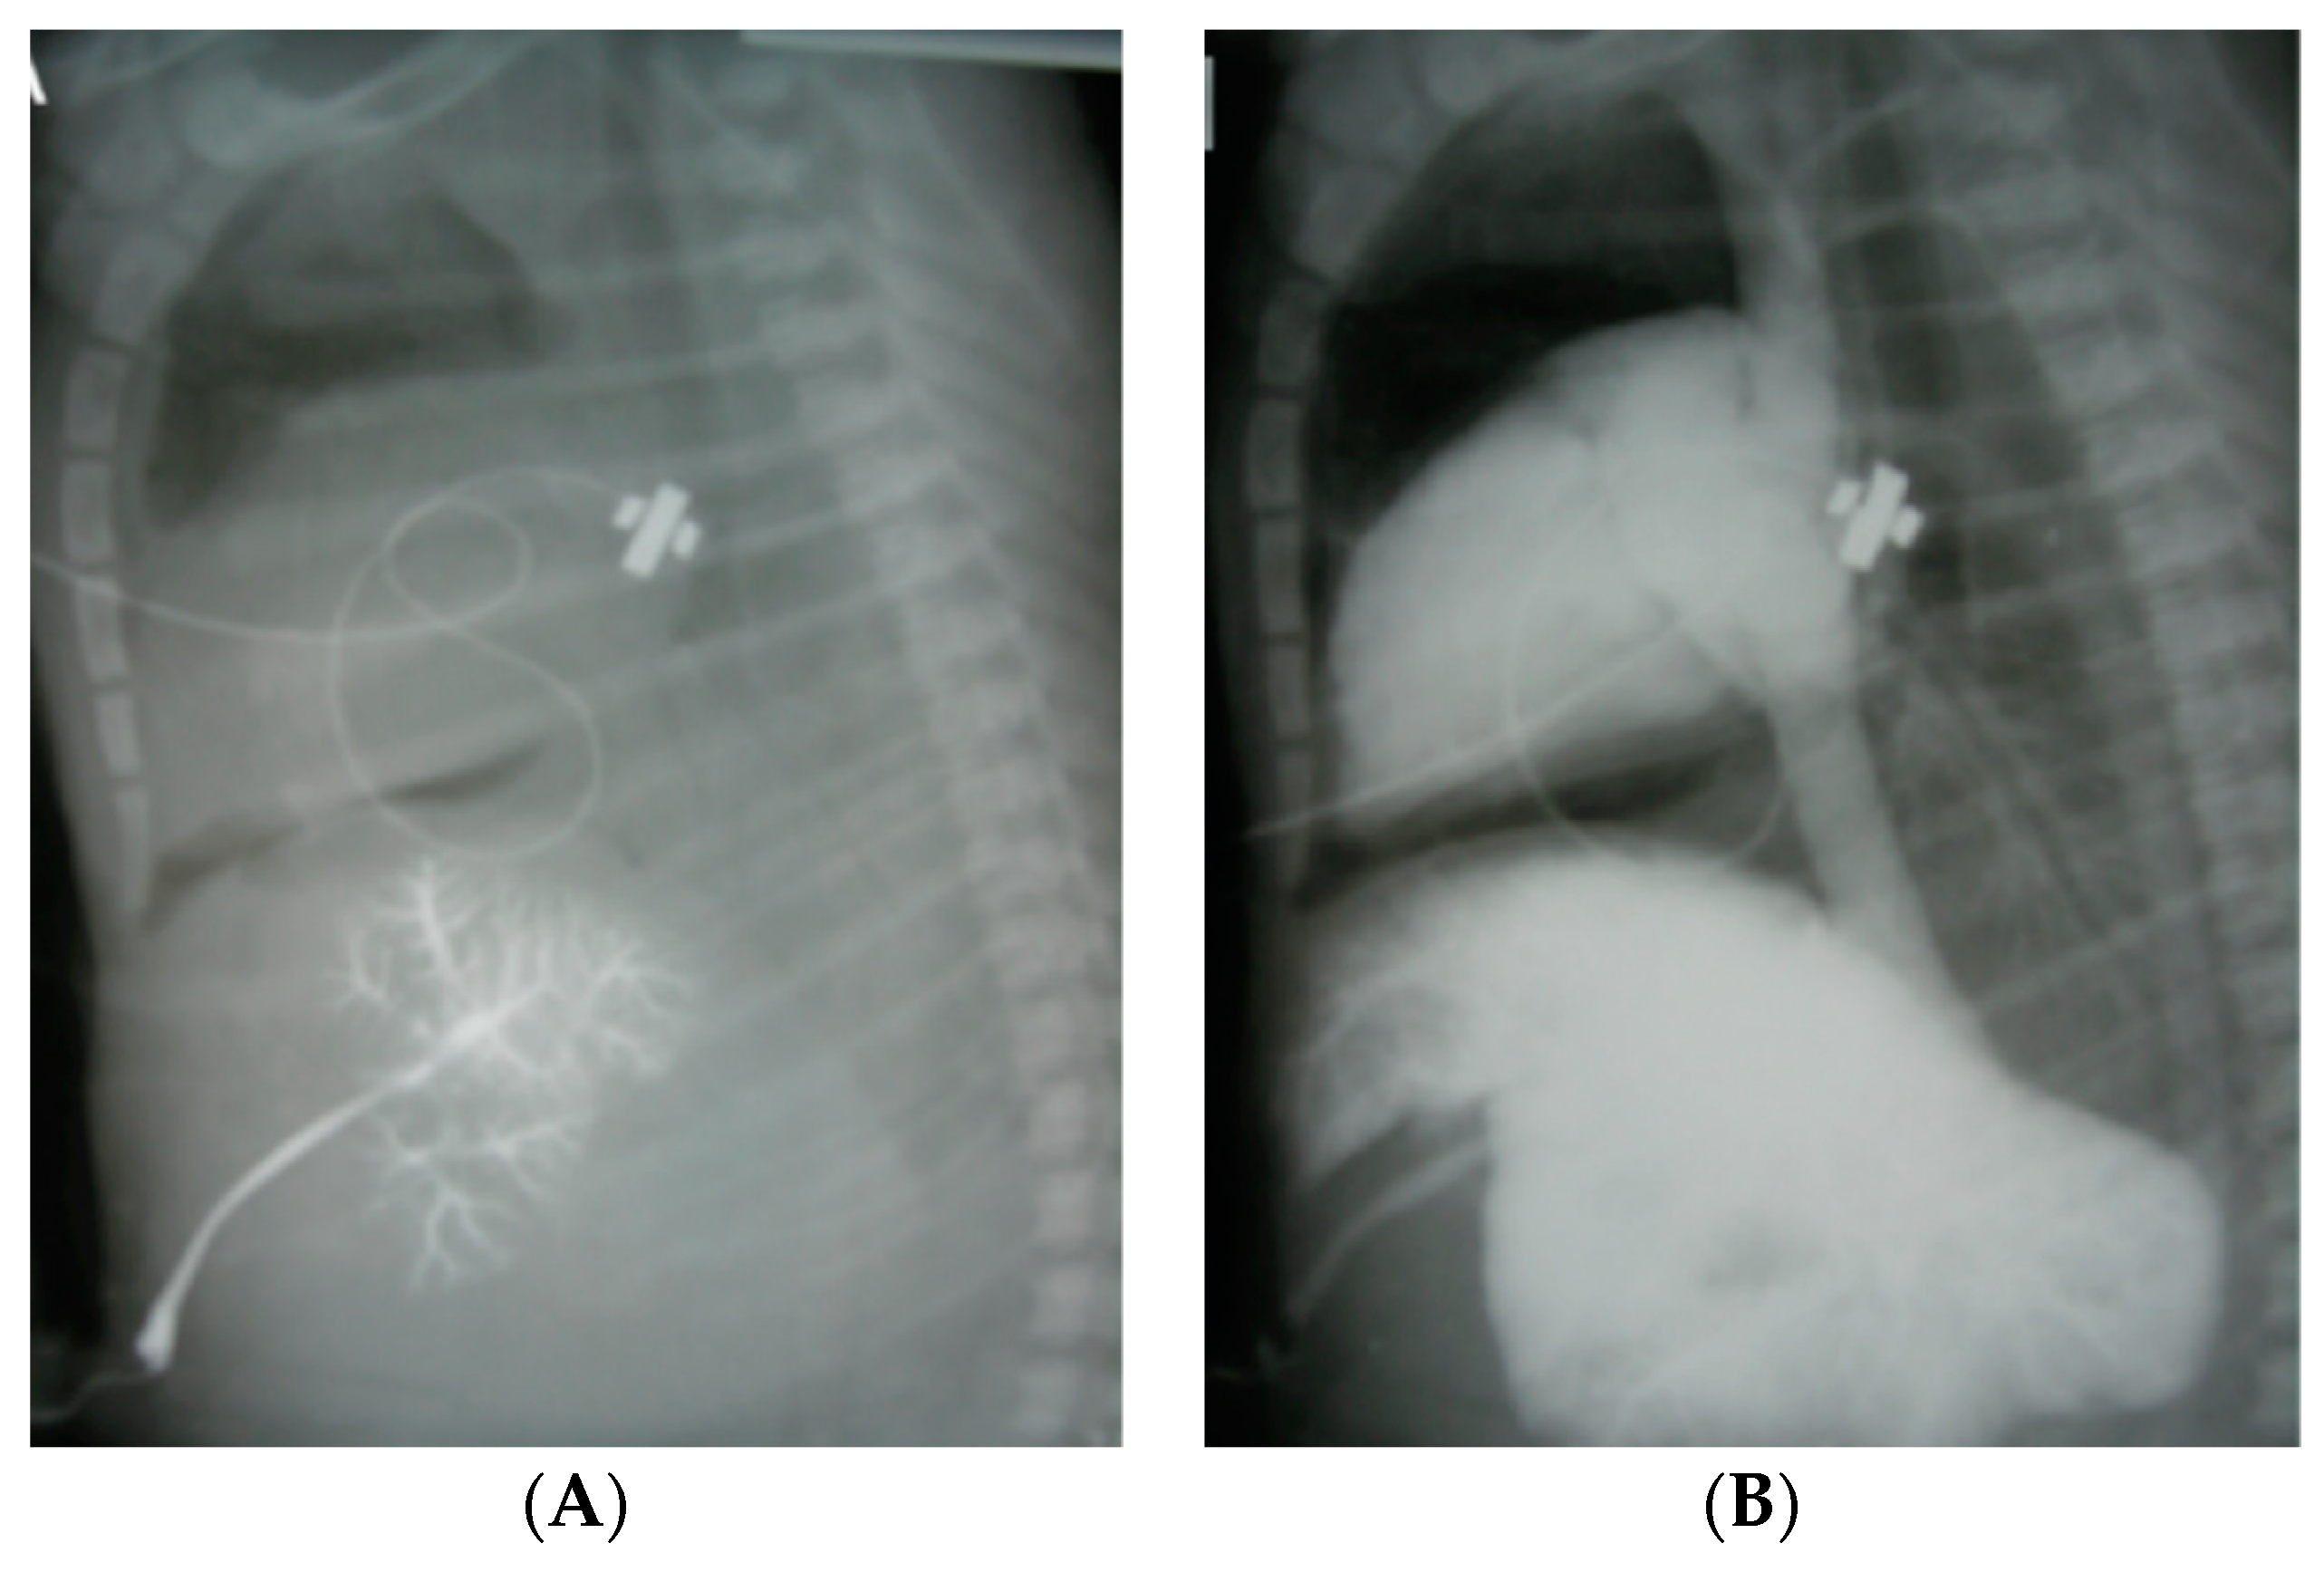

3.1. Intravenous Epinephrine

Low Umbilical Venous Catheter